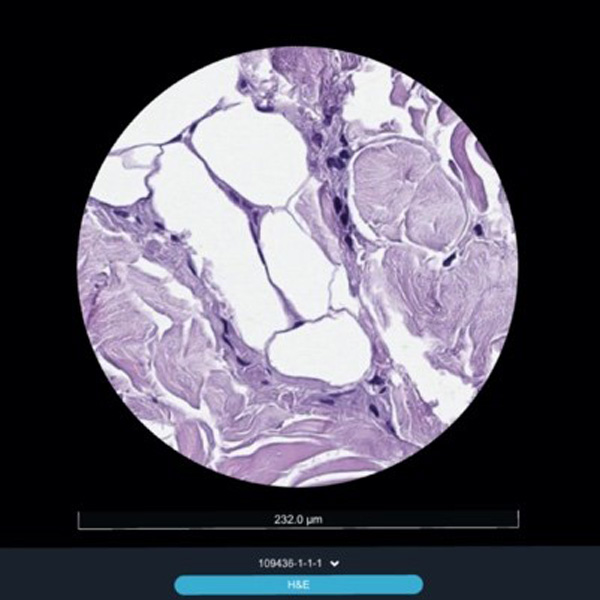

Рис. 1. Виды соединительной ткани в панч-биоптате после курса сеансов воздействия, окраска гематоксилин+эозин: жировые дольки (1) с адипоцитами (1А), строго ориентированные пучки волокон (2Б) в стромальных трабекулах (2). Голубыми стрелками указаны длины адипоцитов.

Прежде всего обращает на себя внимание реакция со стороны клеток жировой ткани: при практически неизменном количестве самих жировых клеток средний размер (объем) каждой жировой клетки существенно сократился почти вдвое.

Предположительно такой эффект достигается за счет активного высвобождения содержимого самих жировых клеток и транспортировкой его в кровеносное русло мелких сосудов соединительной ткани.